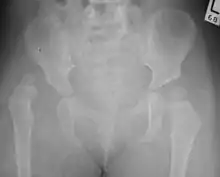

X-Ray Image showing hip dysplasia in a baby